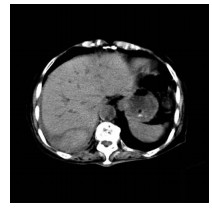

Guideline for ultrasonic diagnosis of liver diseases

Chinese Society of Ultrasound in Medicine, Oncology Intervention Committee of Chinese Research Hospital Society, National Health Commission Capacity Building and Continuing Education Expert Committee on Ultrasonic Diagnosis

2021, 37(8): 1770-1785. DOI: 10.3969/j.issn.1001-5256.2021.08.007

Abstract(3025) HTML (6526) PDF (9311KB)(794)

Abstract:

Ultrasound is a non-invasive, real-time, inexpensive, radiation-free and easily repeatable method, usually used for liver imaging. In recent years, new ultrasound examination techniques for liver diseases such as contrast-enhanced ultrasound and elastography have been rapidly developed, which can effectively identify intrahepatic space-occupying lesions, assess the degree of liver fibrosis and portal hypertension, and monitor the effects of treatment. Therefore, these technologies play an important diagnostic role in clinical liver diseases and have therapeutic interventional value. This guideline classifies the instrument set-up, patient preparation, and physician examination methods through multimodal ultrasound examinations (gray-scale ultrasound, color Doppler ultrasound, contrast-enhanced ultrasound, elastic ultrasound) for liver diseases. In addition, liver diseases multimodal ultrasound technology diagnostic criteria for diffuse hepatic lesions (inflammatory lesions, fibrosis, and sclerosis), multiple space-occupying lesions, and interventional procedures have been defined and standardized. Concurrently, we also recommend the ultrasound monitoring time interval and diagnostic report writing standard for liver diseases.